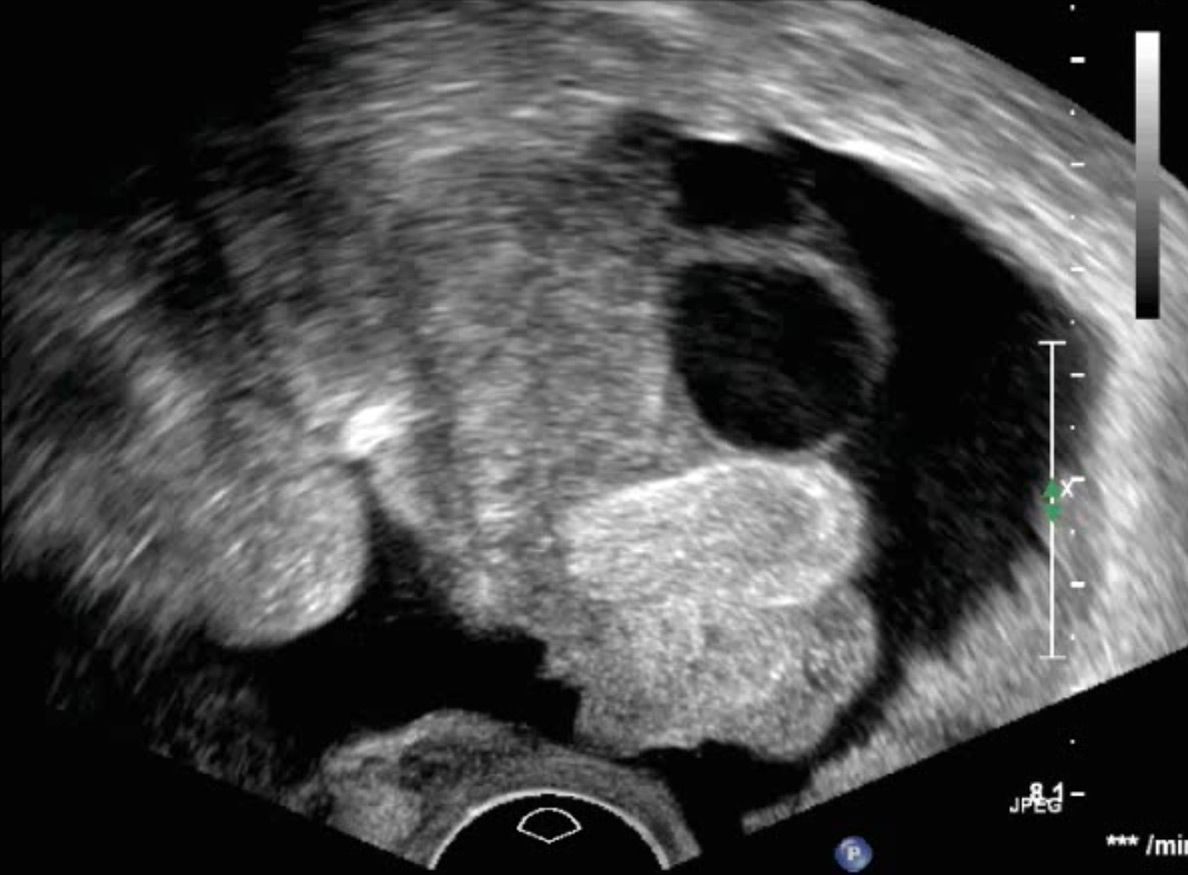

Dermoidzyste

Ovarialkarzinom

Veränderungen des Eierstocks sind gerade vor den Wechseljahren häufig funktioneller Natur und durch zyklusbedingte Einflüsse zu erklären. Diese sollten nicht beunruhigen und sind in aller Regel im natürlichen Verlauf abzuwarten. Raumforderungen am Eierstock können aber auch Beschwerden hervorrufen. Zum anderen sollten sie gegen bösartige Veränderungen abgegrenzt werden. Letztere sind selten, jedoch von ungünstiger Prognose, wenn sie ein fortgeschrittenes Stadium erreicht haben.

Die Abgrenzung zwischen einer einfachen funktionellen Veränderung, einer gutartigen Veränderung oder einer potentiell bösartigen Veränderung sollte primär sonographisch erfolgen.